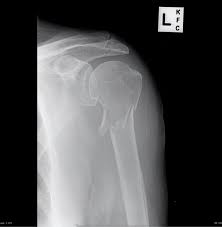

10 x 12 film crosswise 2. The upright position may be more comfortable than the table for some patients. Getting the most from shoulder positioning. Xray examination of the clavicle radiography of clavicle is routinely done in radiology department in both ap and ap axial projection. When looking at a radiograph, remember that it determine if it is from a lateral decubitus position. Bones • sternum • clavicles • scapulae • ribs • spine. In this position, the image will clearly show the condition of the. Boning up on humerus, clavicle, and ac joint positioning. In addition to covering anteroposterior and lateral radiographs, dr. Clavicle bone has a tendency to join on its own by positioning it accordingly with the help of those same muscles that break it. The position of the patient should be either upright or supine. Hand, thumb, fingers, wrist, forearm, elbow, humerus, shoulder and clavicle. Boning up on humerus, clavicle, and ac joint positioning.

In this position, the image will clearly show the condition of the. In addition to covering anteroposterior and lateral radiographs, dr. Ahmad explains how to work with a patient in the supine or upright position, as well. Boning up on humerus, clavicle, and ac joint positioning. The position of the patient should be either upright or supine. Getting the most from shoulder positioning. Xray examination of the clavicle radiography of clavicle is routinely done in radiology department in both ap and ap axial projection. Proper positioning for the pelvis and proximal femur the lowdown on lumbar spine positioning radiographic positioning techniques for the cervical spine boning up on humerus, clavicle, and ac joint positioning getting the most from shoulder. Digit imaging requires diligent positioning. Hand, thumb, fingers, wrist, forearm, elbow, humerus, shoulder and clavicle. Additional imaging of the lung apices • properly positioned (not rotated or angulated): Please remove all obscuring objects and, as always, practice proper radiation protection. Bones • sternum • clavicles • scapulae • ribs • spine.

Getting the most from shoulder positioning. Outline • plain films different views • positioning • interpretation of the plain film. The position of the patient should be either upright or supine. Boning up on humerus, clavicle, and ac joint positioning. The upright position may be more comfortable than the table for some patients. Positioning the catheter tip too proximally, for example in the right or left brachiocephalic veins, is associated with increased risk of line infection and thrombosis. Assessing the image quality, ripe mnemonic is used; Hand, thumb, fingers, wrist, forearm, elbow, humerus, shoulder and clavicle.